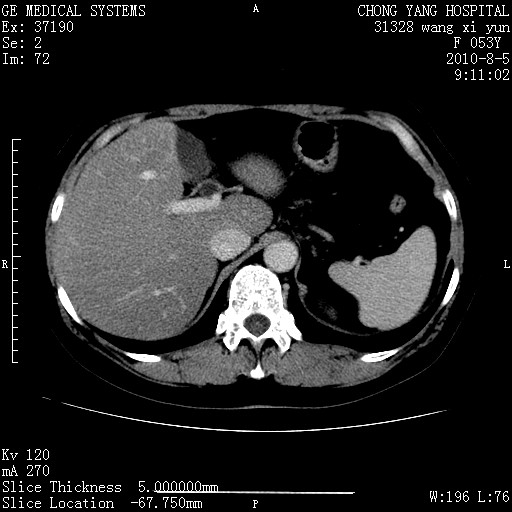

标题: CT28214:F41Y 血尿二十天,建议盆腔平扫加增强。

胆管细胞ca?

1)考虑肝左叶胆管细胞癌。2)脂肪肝。

支持胆管细胞ca。